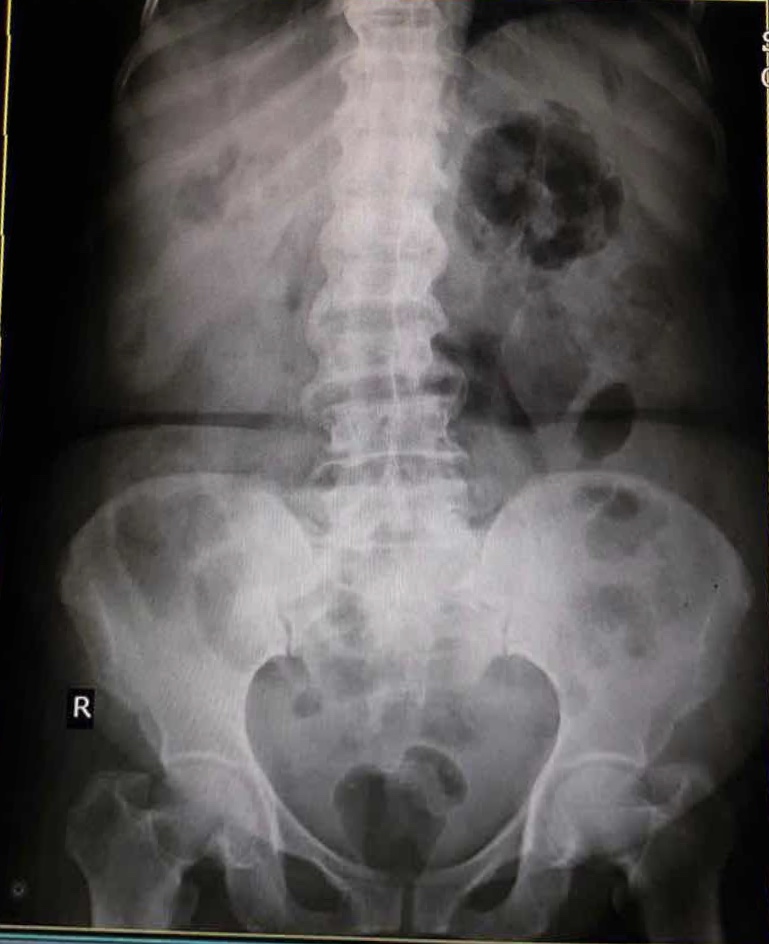

X Ray KUB on 8/2/22:

USG DONE ON 8/2/22:

1. B/L hydronephrosis

2. Right simple renal cortical cyst

3. Grade I fatty liver

NCCT KUB:

1. Pneumoperitoneum with ?left perinephric abscess.

2. Air foci in upper calyx of right kidney- ? Emphysematous pyelonephritis

3. Mild ascites.